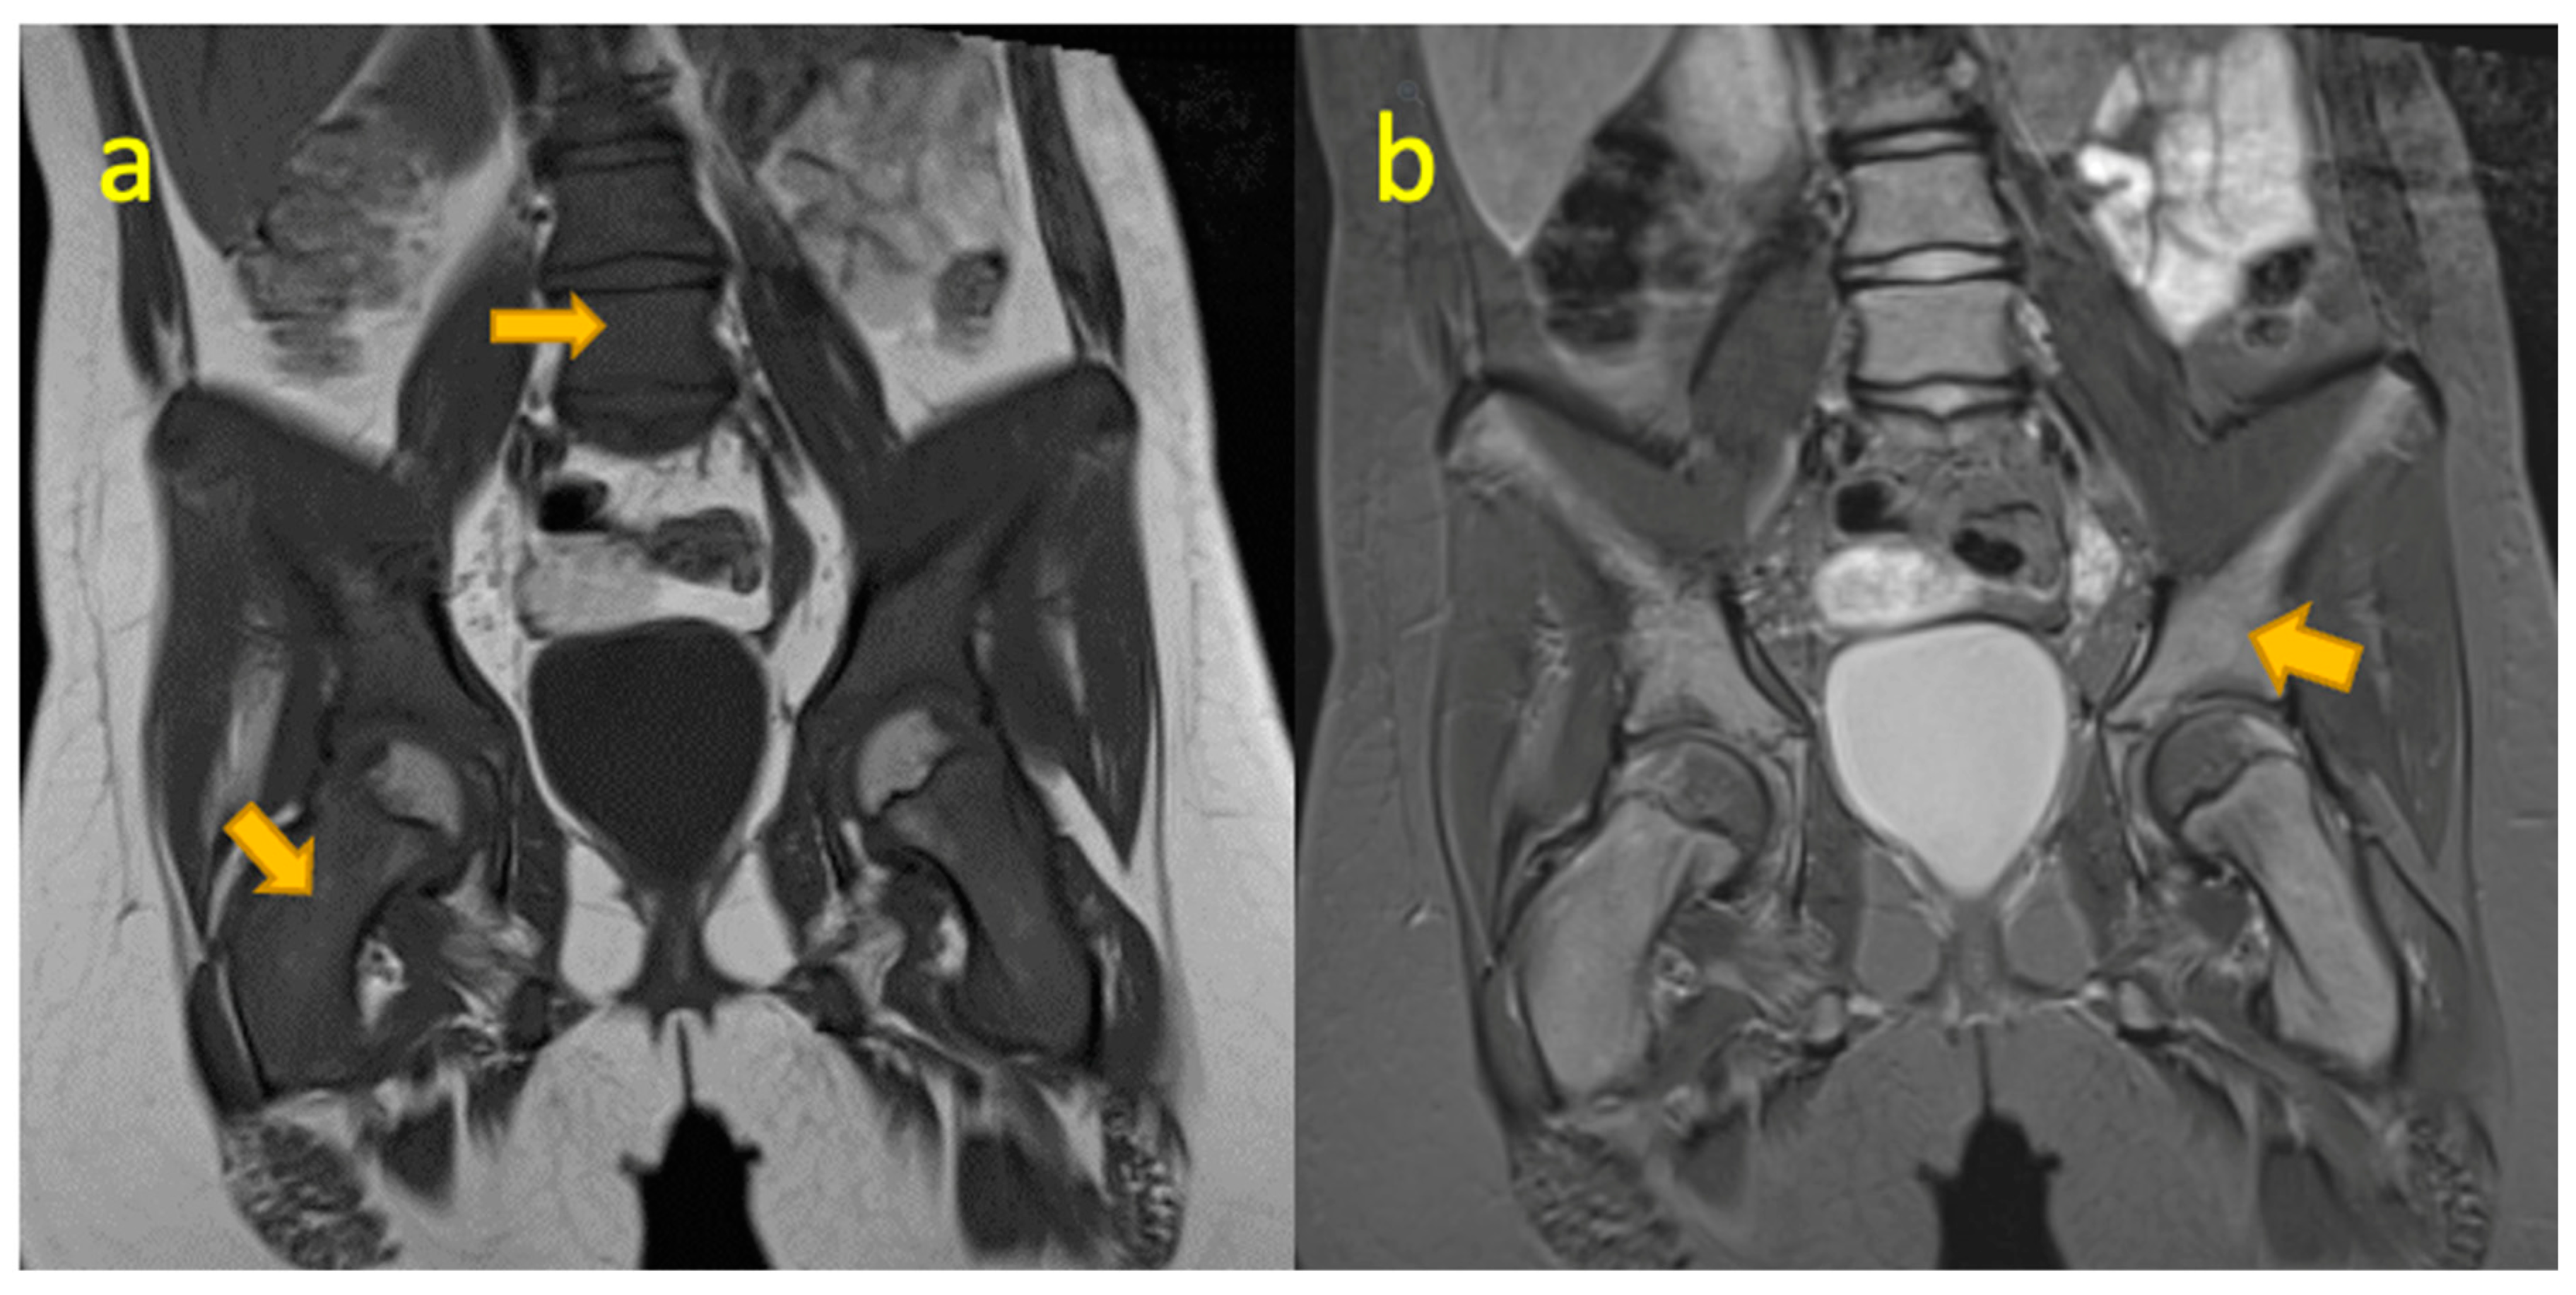

14. Lumbar Spine Discitis

16. Stress Fracture of Sacral Ala

- Fernandez, M.; Carrol, C.L.; Baker, C.J. Discitis and vertebral osteomyelitis in children: An 18-year review. Pediatrics 2000, 105, 1299–1304. [Google Scholar] [CrossRef]

- Fuster, D.; Tomas, X.; Mayoral, M.; Soriano, A.; Manchon, F.; Cardenal, C.; Monegal, A.; Granados, U.; Garia, S.; Pons, F. Prospective comparison of whole-body (18)F-FDG PET/CT and MRI of the spine in the diagnosis of haematogenous spondylodiscitis. Eur. J. Nucl. Med. Mol. Imaging 2015, 42, 264–271. Available online: https://pubmed.ncbi.nlm.nih.gov/25186431/ (accessed on 15 October 2024). [CrossRef] [PubMed]

- Modic, M.T.; Feiglin, D.H.; Piraino, D.W.; Boumphrey, F.; Weinstein, M.A.; Duchesneau, P.M.; Rehm, S. Vertebral osteomyelitis: Assessment using MR. Radiology 1985, 157, 157–166. [Google Scholar] [CrossRef] [PubMed]